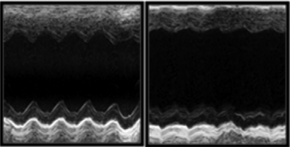

心肌梗死模型

心肌梗死动物模型主要应用于急性心肌梗死等相关研究。米乐生物通过冠脉LAD结扎的方式模拟急性心肌缺血的病理过程。造模后可通过心脏超声、TTC染色等指标检测判断是否造模成功。米乐生物手术经验丰富、成模率高、死亡率低、周期短。

心肌缺血再灌注模型

心肌缺血再灌注动物模型主要应用于心肌缺血再灌注损伤等相关研究。米乐生物通过冠脉LAD结扎后松开的方式模拟心肌缺血再灌注损伤的病理过程。造模后可通过心脏超声、心电图、TTC-Evans blue染色等指标检测判断模型是否成功构建。米乐生物手术经验丰富、成模率高、死亡率低、周期短。